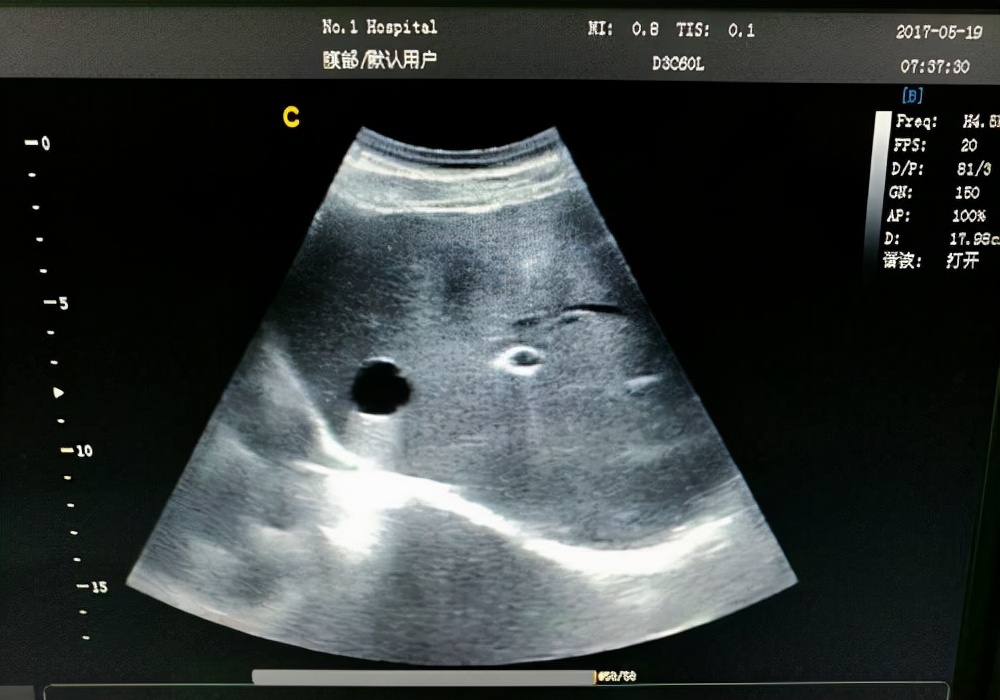

2、肝囊肿

肝囊肿是比较常见的肝脏疾病,很多人在听到囊肿时会认为是可怕的肿瘤,都认为要治疗或者进行手术切除,却不知有些肝囊肿不需要理会,只需要定期检查即可。

但如果发现肝囊肿直径超过5厘米或者有明显症状,如 腹痛、上腹不适等,就需要及时采取相对应治疗措施 。在目前肝囊肿最佳治疗方法是进行手术治疗,不仅安全,创伤性也比较小。